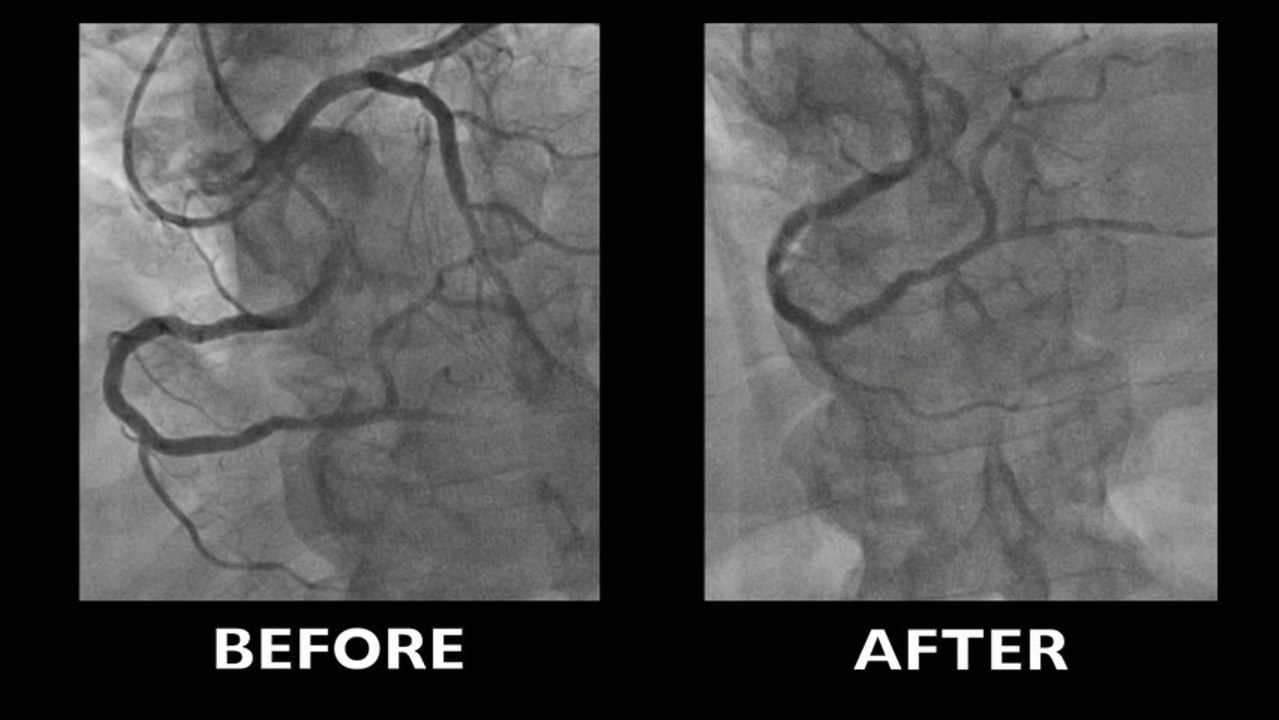

Complex CTO-PCI of ostial long LAD occlusion

Long and calcified ostial and proximal LAD occlusion